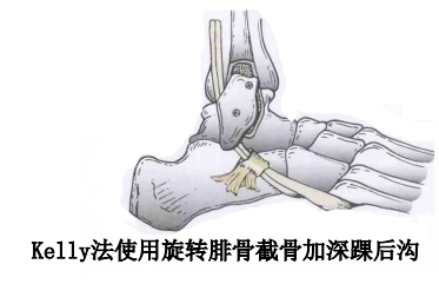

通过切除腓骨后方部分骨质,可以加深腓骨沟,改变、并增加了腓骨肌腱的稳定。

内镜下腓骨沟加深手术

大部分急性损伤可以使用直接缝合修复,对慢性损伤则需根据患者的具体病理改变选择,如单纯的支持带结构损伤,可以直接缝合修复。如果直接修复不够稳定,需用其他组织加强。如果腓骨外踝窝较浅时,就需要使用加深手术。